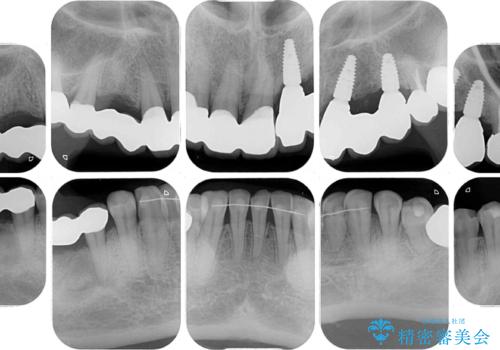

- 割れていると言われて放置してしまった歯や、前歯のデコボコなどが気になるとのことで来院された患者様です。

左上の歯は割れてしまっており、抜歯のうえインプラント治療が必要であり、他にも抜歯の必要な歯がある状態でした。

上顎はほぼ全ての歯をセラミッククラウンにて補綴治療を行う必要があるため、気になるデコボコや深い咬み合わせを改善するために下顎と上顎の臼歯部の矯正治療を行うこととしました。

並行して左下にはインプラントを埋入し、矯正治療を終えると同時に補綴治療を行うこととしました。